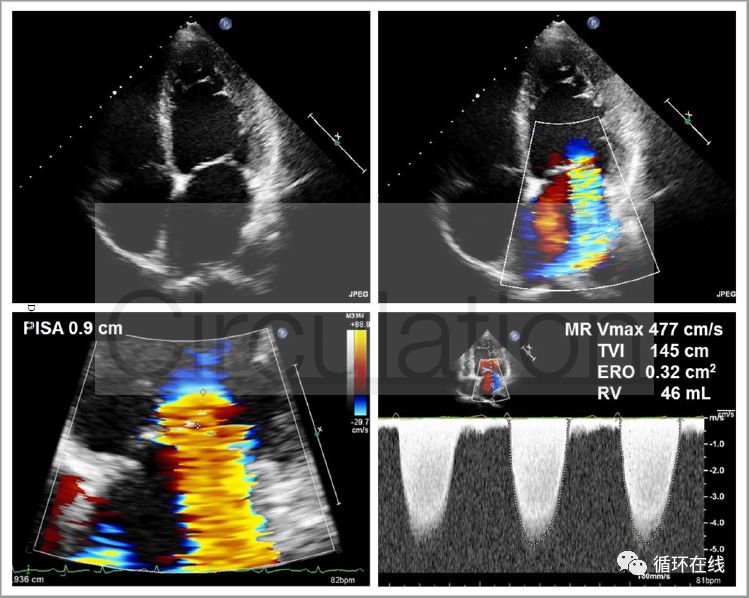

图7(A):基线超声心动图显示重度功能性MR.采用PISA半径和MR射流的峰值速度计算

图7(B):使用沙库比曲/缬沙坦治疗12个月后二尖瓣返流改善,EROA显著下降